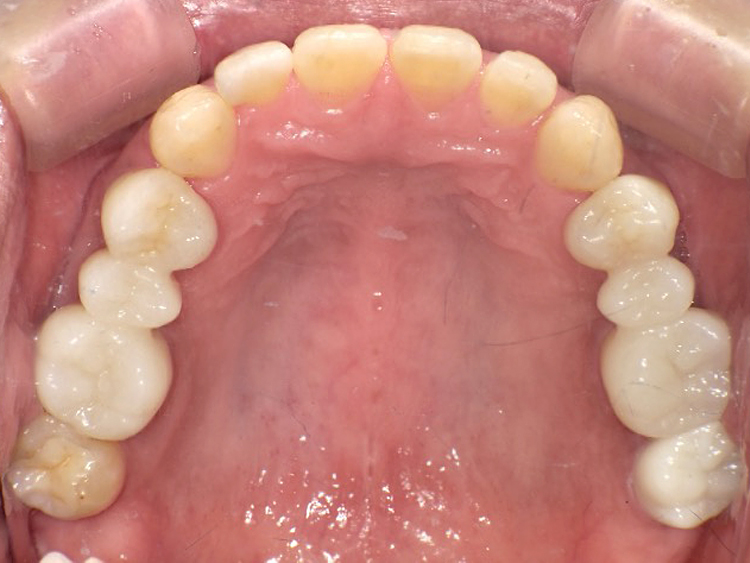

症例4

Before

After

| 主訴 | 上下前歯のがたつき |

|---|---|

| 年齢 | --- |

| 治療 期間 |

約9ヶ月 |

| 治療 内容 |

インビザラインiGoで上下顎の治療。 |

| 治療費 | ¥550,000(税込)/調整料含む |

| 治療のリスク | 矯正終了後は、リテーナーを指示通りに使用し、歯の後戻りを防ぐ必要があります。 |